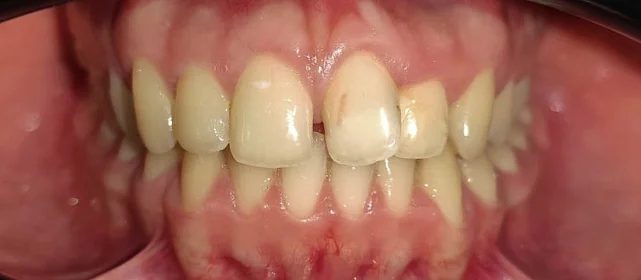

Исправление прикуса на брекетах за 28 месяцев перед протезированием

Неровные зубы, неправильный прикус.

Нарушение соотношения челюстей и неправильное положение зубов — ряды смыкались некорректно, зубы стояли со смещением.

Проблема: Пациентка обратилась с жалобами на неровные зубы и неправильный прикус. Челюсти смыкались некорректно, зубы стояли со смещением. Часть зубов нуждалась в восстановлении коронками, но ставить их на кривой ряд с неправильным прикусом значит заведомо сократить им срок службы. Нагрузка будет распределяться неравномерно, и конструкции быстро выйдут из строя. Поэтому первый этап — ортодонтия, второй — протезирование.